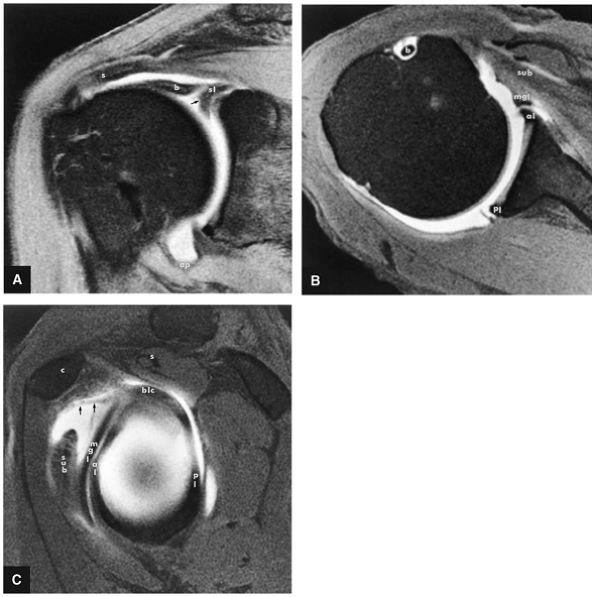

FIGURE 8.6 ● Routine MR arthrography with FS T1-weighted (A) coronal oblique, (B) axial, and (C) sagittal oblique (at the level of the glenohumeral joint) images. s, supraspinatus tendon; b, biceps tendon; SL, superior labrum; arrow, conjoined origin of the superior and middle glenohumeral ligaments; AP, axillary pouch; al, anterior labrum; PL, posterior labrum; MGL, middle glenohumeral ligament; sub, subscapularis tendon; c, coracoid; BLC, biceps labral complex; small arrows, superior glenohumeral ligament.